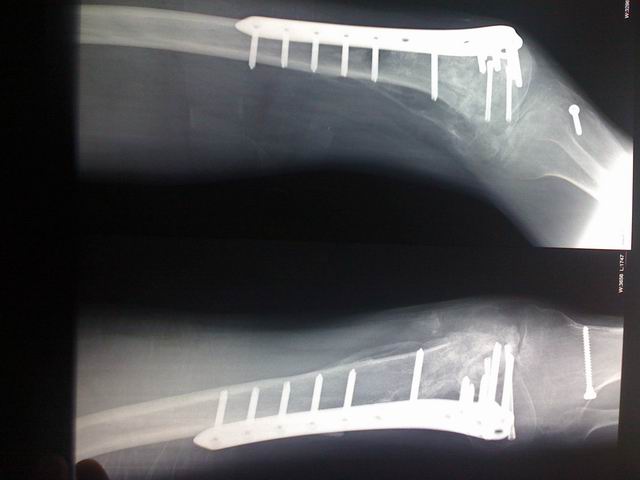

宗亲们好,这是过来拍的片子。

调整大小 IMG_0031.jpg

调整大小 IMG_0032.jpg

调整大小 IMG_0033.jpg